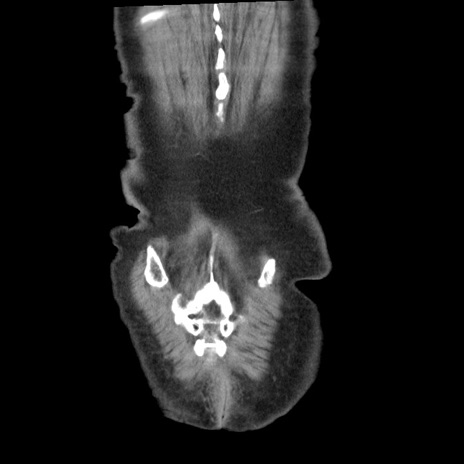

横断像

矢状断像